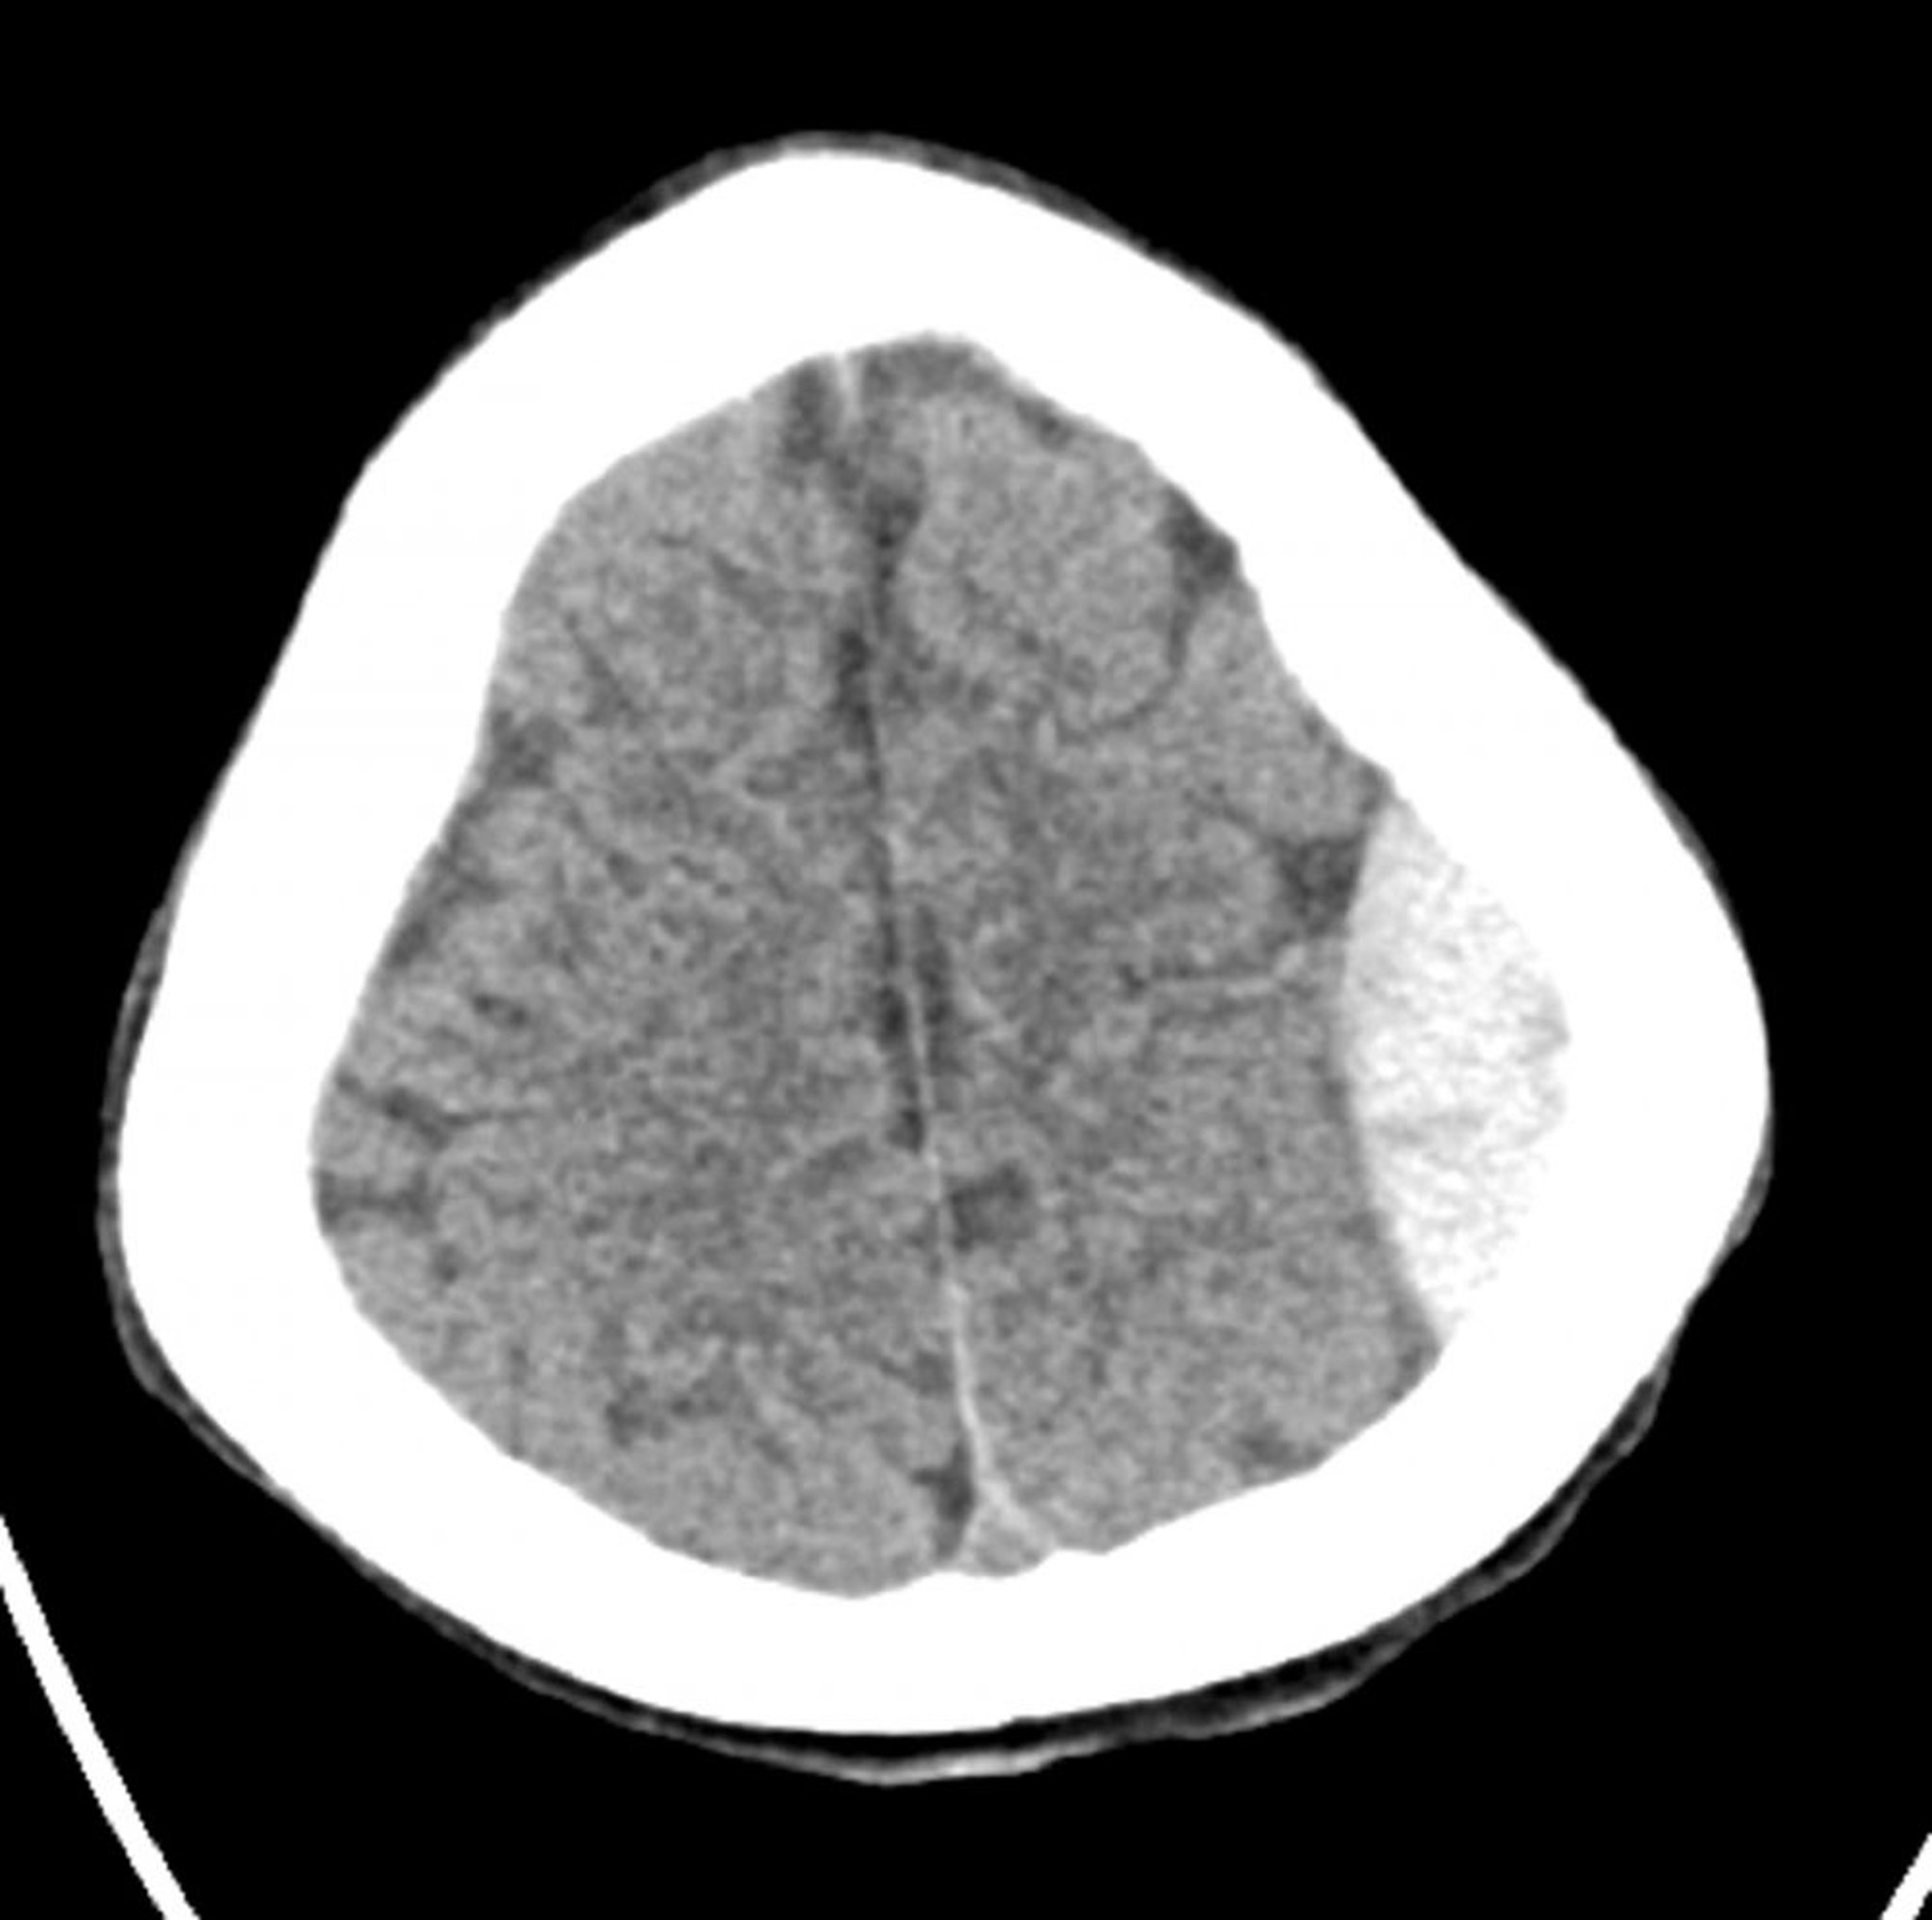

Hémorragie épidurale (TDM axiale)

Hyperdensité classique en forme de lentille qui ne s'étend pas à travers les lignes de suture.

© 2017 Elliot K. Fishman, MD.